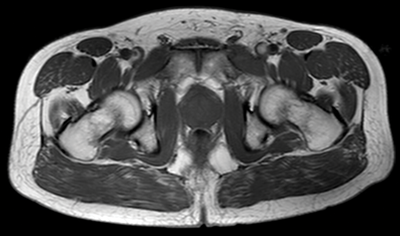

The normal prostate gland demonstrates intermediate to low signal intensity on T1-weighted imaging [4]. There is insufficient soft-tissue contrast resolution on the T1W images to distinguish the intraglandular architecture and therefore this sequence is not used for tumour localisation (Figure 1).

Figure 1: Axial T1 image showing homogeneous low signal appearance of the prostate.